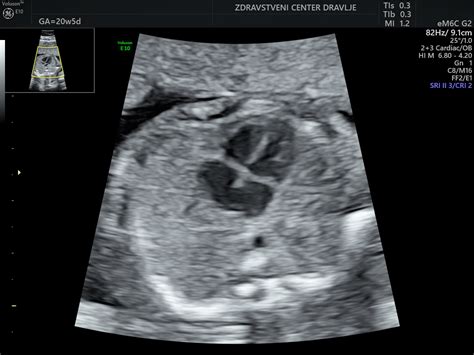

Ultrazvočni pregled v tem tednu je lahko nadvse zanimiv! Ne le, da boste videli otročka na zaslonu, lahko boste videli tudi nekaj čudovitih podrobnosti, kot so možganske poloble in srčni prekati. Trenutek, ko ugotovite, ali gre za fantka ali deklico, je res vznemirljiv. Če gre za deklico, ima v maternici že vsa jajčeca, ki jih bo imela v življenju - in to približno šest milijonov! Če pa pričakujete fantka, se testisi spuščajo v skrotum (mošnjo). Nekateri starši raje počakajo do rojstva, da ostane presenečenje. Morda lahko prosite zdravnika, da informacijo zapiše in jo shrani v kuverto, ki jo nato odnesete domov. Nato lahko pripravite zabavo, na kateri boste z družino in prijatelji razkrili preseneenje. Če nosečnost poteka brez zapletov, je to morda vaš zadnji ultrazvok, zato je pametno, da sedaj zaprosite za ultrazvočne posnetke.